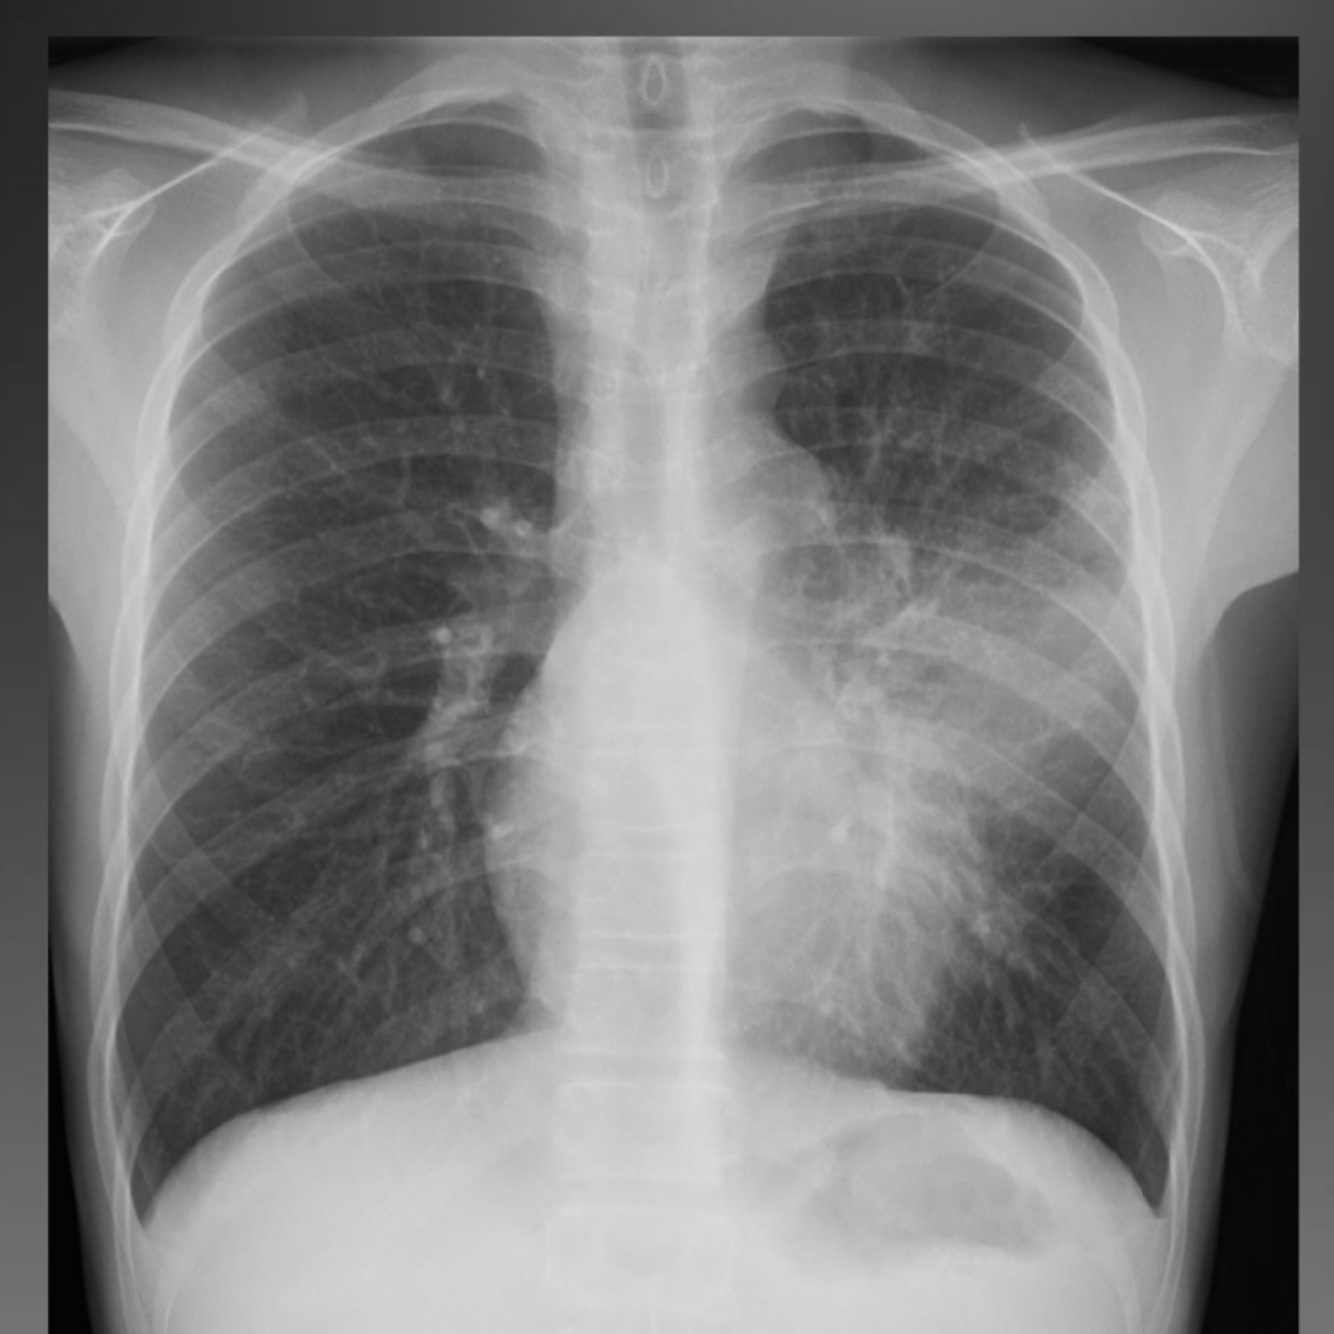

Q

A

Progressive Primary Tuberculosis

Progressive primary tb

Less common

Rapidly progressive disease

CXR: extensive consolidation and

cavitation

Can mimic post primary MTB

infection